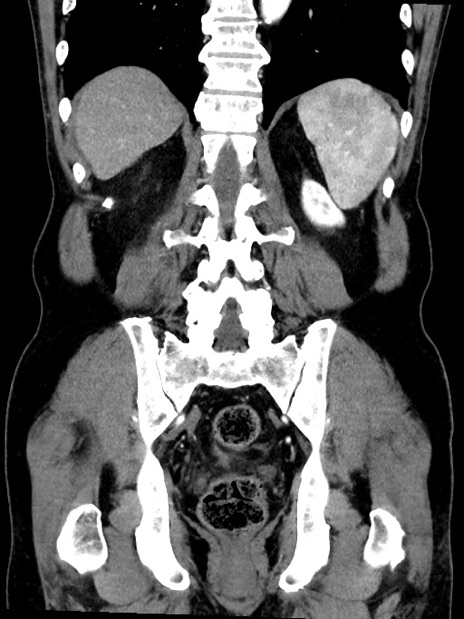

症例35(冠状断像)

【症例】70歳代 男性

【主訴】腹部膨満、嘔吐

【現病歴】昨日より腹部膨満感出現。本日増悪し、仙痛出現。嘔吐あり、受診。

【既往歴】糖尿病、胆摘後

【身体所見】BP 149/80mmHg、HR 74/min、BT 35.9℃、腹部:膨満、軟、圧痛なし。腸雑音減弱あり。上腹部正中切開瘢痕あり。

【データ】WBC 13500、CRP 1.72